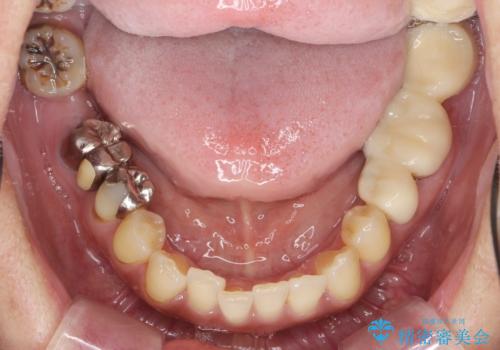

- 「歯の見た目が悪く、奥歯も噛みづらい、しっかりと全体的に治療したい。」と全顎的な治療を希望され来院されました。

虫歯・感染根管・予後不良歯・欠損・不正咬合、複合的な問題を一つづつ丁寧に解決し、将来に渡り不安のない口腔内環境にすべく全体的な総合治療を行っていきます。